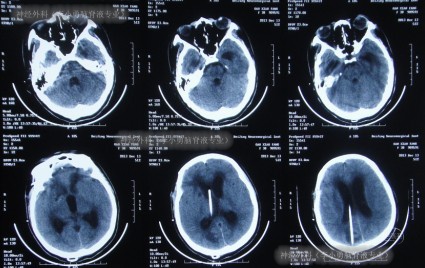

2013年11月18日即术后第14天(腰大池外引流管拔除后第6天),神志转清,右手能写字,但存在吞咽障碍、发音障碍、左侧肢体无力表现,复查头颅CT(图-5)示水肿减轻,脑室稍扩张。考虑患者处于恢复期,脑室可逐渐恢复正常,并将其转入普通病房继续治疗。

图-5:术后14天头颅CT

继续治疗14天内,患者逐渐出现表情呆滞,反应迟钝,昏睡,在2013年12月2日即动脉瘤夹闭术后28天,复查头颅CT示脑室扩张加重及脑室周围水肿明显(图-6)。

图-6:术后28天头颅CT

患者之后病情仍逐渐恶化,在2013年12月10日即分流术后8天(抗感染治疗6天后),再次出现昏睡,体温高达38.5 ℃左右,复查头颅CT示脑室扩张较术前没有变小或仍然较为严重的程度(图-7)。

图-7:分流术后8天头颅CT

患者体温逐渐恢复正常,但意识仍无明显改善,处于昏睡状态,于2013年12月13日即分流术后11天,查头颅CT(图-8)示脑室仍显著扩张。

图-8:分流术后11天头颅CT